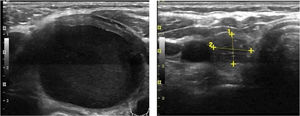

Mean maximum cyst diameter before drainage was 3.1±1.2cm with a calculated median initial volume of 12.7 (5.4–21.7)ml. Median total volume extracted from the cysts in all procedures performed in one patient was 13.0 (6.2–37.0)ml. Panels A and B in Fig. 1 show respectively the initial and final ultrasound appearance of a treated thyroid cyst.

With regard to complications, reported pain during the procedure was mild in 55.2% and moderate in 23.6% of cases. Of note, virtually absent pain perception was observed in 21.2%. In all cases, this pain sensation was transient with relief within minutes. Two patients presented intranodular bleeding in one PEIT, which was self-limited with external compression and local cold application with spontaneous partial reabsorption and totally with a subsequent PEI performed two weeks after (Fig. 2). Cyst recurrence in cases treated more than once occurred from hours to a few days after each PEIT procedure (Fig. 3).